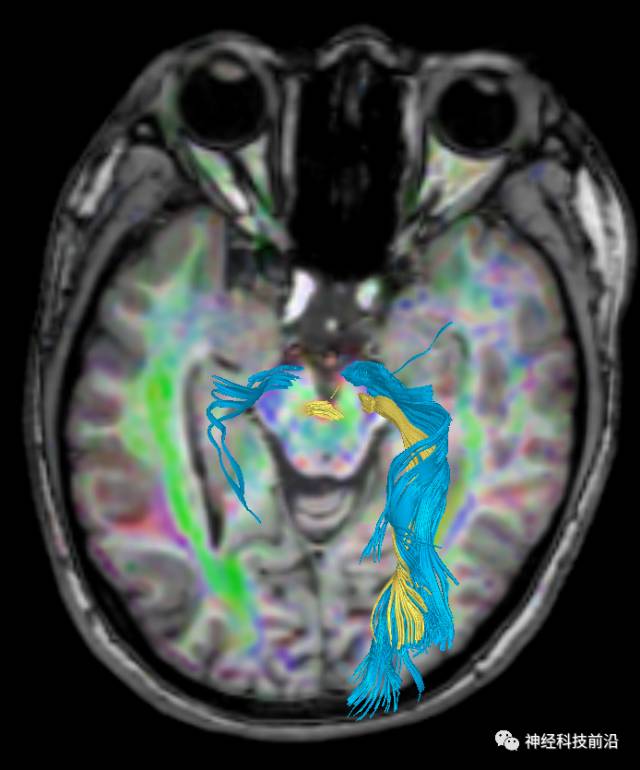

下面为皮质脑桥束的走形方位

皮质脑桥束与脑干高信号(黄色)纤维束